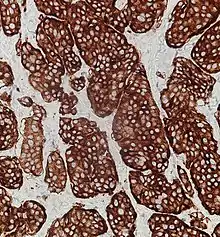

Neuroendocrine tumors, despite differing embryological origin, have common phenotypic characteristics. NETs show tissue immunoreactivity for markers of neuroendocrine differentiation (pan-neuroendocrine tissue markers) and may secrete various peptides and hormones. There is a lengthy list of potential markers in neuroendocrine tumors; several reviews provide assistance in understanding these markers.[67][59] Widely used neuroendocrine tissue markers are various chromogranins, synaptophysin and PGP9.5. Neuron-specific enolase (NSE) is less specific.[2][6] The nuclear neuroendocrine marker insulinoma-associated protein-1 (INSM1) has proven to be sensitive as well as highly specific for neuroendocrine differentiation.[68]